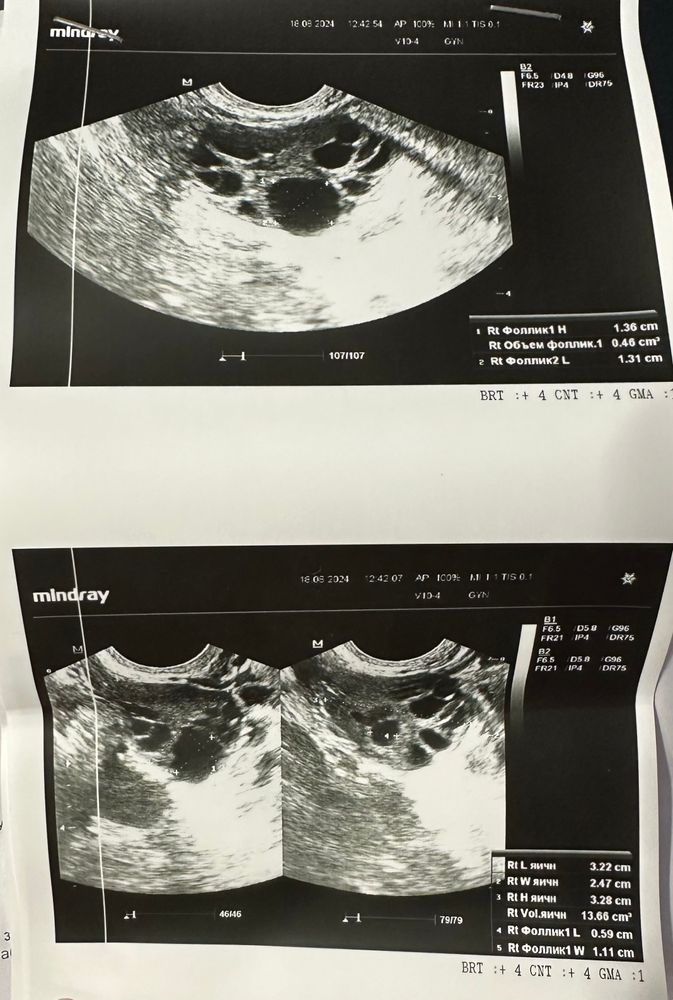

Тест на овуляцию был положительный весь день на 18 дц, потом пошел на спад. Сегодня на 22 дц на узи сказали, что эндометрий 1 см и дф в правом яичнике 14 мм. Еще поставили мфя. Врач сказала сдать прогестерон на 25-26, но это не будет слишком рано для точного результата? И стоит ли вообще ждать овуляцию? А то как-то все затянулось в этом цикле

При СПКЯ И МФЯ не всегда показательны тесты на овуляцию. Я бы подождала еще, по идее через пару дней уже дорастет. Прогик сдавать не имеет смысла, проще повторить узи. ДФ у вас 12мм, ориентировочный рост 1-2мм в сутки.